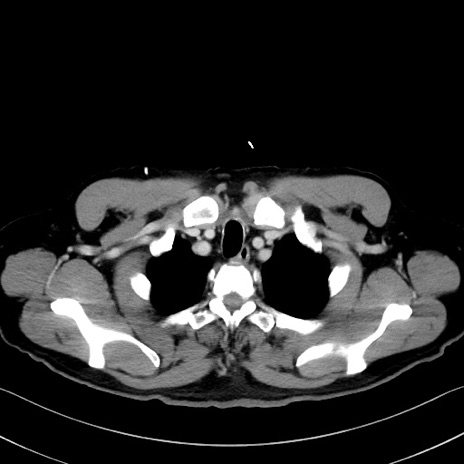

症例35(横断像)

【症例】70歳代 男性

【主訴】腹部膨満、嘔吐

【現病歴】昨日より腹部膨満感出現。本日増悪し、仙痛出現。嘔吐あり、受診。

【既往歴】糖尿病、胆摘後

【身体所見】BP 149/80mmHg、HR 74/min、BT 35.9℃、腹部:膨満、軟、圧痛なし。腸雑音減弱あり。上腹部正中切開瘢痕あり。

【データ】WBC 13500、CRP 1.72